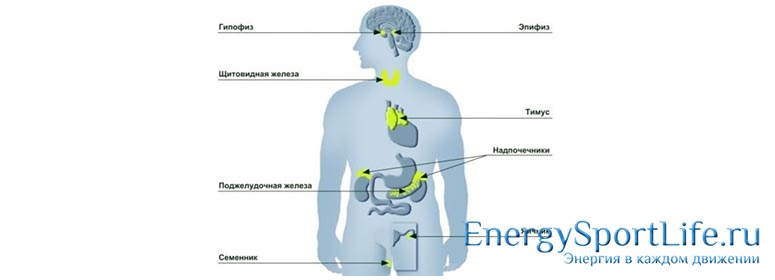

Эндокринная система

Эндокринная система – это совокупность биологически активных элементов, которые регулируют рост, вес, размножение и многие другие жизненно важные процессы организма.

Выделяют главные части эндокринной системы :

— Гипофиз;

— Эпифиз;

— Щитовидная железа;

— Тимус (вилочковая железа);

— Надпочечник;

— Поджелудочная железа;

— Яичники (вырабатывают женский половой гормон);

— Семенники (вырабатывают мужской половой гормон).

Анатомия органов эндокринной системы

Под эндокринными органами подразумевают комплекс различных желёз, которые синтезируют в организме специальные вещества — гормоны, отвечающие за рост, развитие и полноценное протекание многих биологических процессов. К эндокринной группе органов относятся:

Любое, даже самое минимальное, повреждение эндокринных желёз может стать причиной серьёзного гормонального дисбаланса, который, в свою очередь, приведёт к сбоям в работе организма в целом. Именно поэтому исследование крови на уровень гормонов является одним из базовых исследований в диагностике различных патологий, особенно связанных с репродуктивной функцией и всевозможными нарушениями развития.